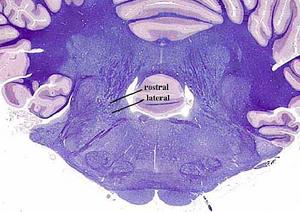

En el desarrollo embriológico, el crecimiento del IV ventrículo trae consigo el desplazamiento de las láminas alares lateralmente a las láminas basales.

Así, en comparación con la médula espinal, en la que los núcleos nerviosos están formados por aglomeraciones de neuronas dispuestas en columnas contínuas a todo lo largo de ella, en el tronco del encéfalo se presentan los núcleos nerviosos constituidos por columnas discontínuas de células.

secciones transversales a diferentes niveles del tronco del encéfalo mostrando la localización de los núcleos neuronales eferentes de los nervios craneales

EFERENTES:

somatoeferentes (SE) : inervan músculos esqueléticos

visceroeferentes(VE): parasimpáticos